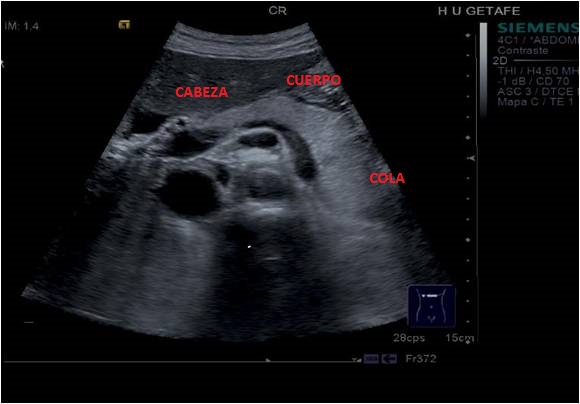

Hemos comentado que el Páncreas tiene varias regiones, ecográficamente nos importan 3, Cabeza, Cuerpo y Cola.

Cuando localicemos el Páncreas lo repasaremos y estudiaremos comprobando que sea normal tanto en axial o transverso como en longitudinal. Ecográficamente el Páncreas es una estructura alargada, hiperecogénica y homogénea, así:

Al tener tres zonas anatómicas, tenemos que estudiarlas separadamente, debiendo colocar el transductor de manera adecuada a cada una de ellas. Son estas: